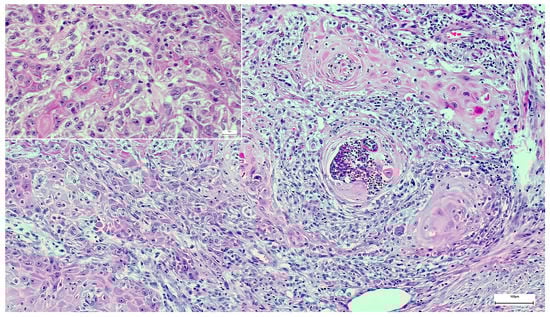

A Wolf in Sheep’s Clothing: Collision of Melanoma and Keratoacanthoma

:1. Case Presentation

2. Discussion